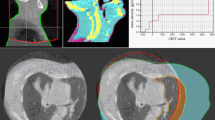

Figure 3 shows the central slice of the CT data for measurement series (1) including positions for carbon ion radiographic measurements. The PMMA box was positioned on the treatment couch according to the room laser system with CT slices orthogonal to the beam direction. To compare residual ranges behind soft tissue materials to range in water, additional measurements with the PMMA box filled with water were performed.

Carbon ion radiography measurement positions. Central slice of the PMMA phantom filled with different tissue samples (series 1). Carbon ion radiography measurements were performed at two different phantom positions, indicated by crosses. Positions selected for carbon ion radiographic measurements are indicated by squares and circles.